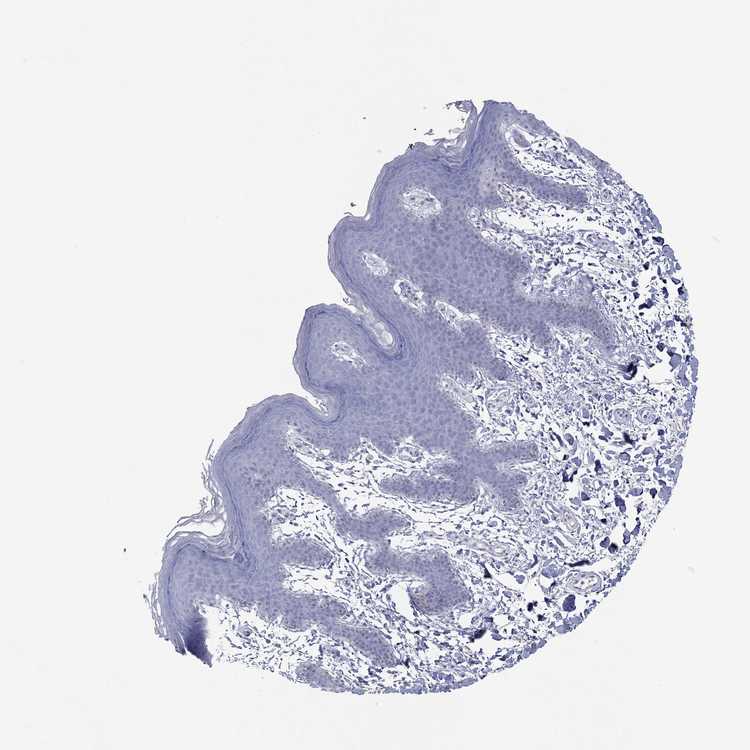

SKIN 2 - Antibody stainingi

Antibody staining in the annotated cell types in the current human tissue is reported as not detected, low, medium, or high, based on conventional immunohistochemistry profiling in selected tissues. This score is based on the combination of the staining intensity and fraction of stained cells.

Each image is clickable and will lead to virtual microscopy that enables deeper exploration of all samples and also displays staining intensity scores, fraction scores and subcellular localization as well as patient and tissue information for each sample.

Antibody HPA079265

Epidermal cells Not detected